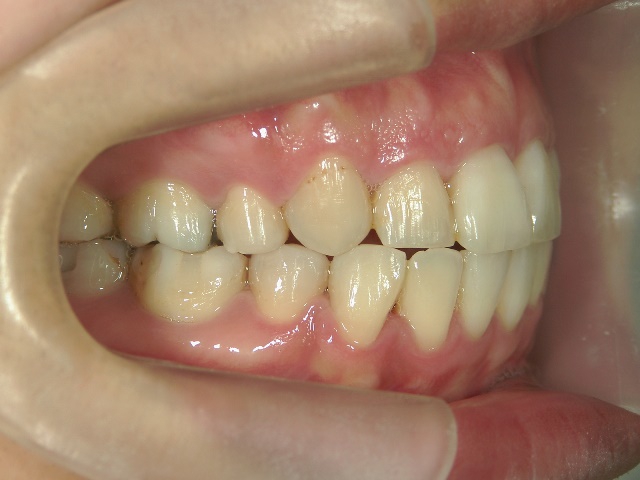

矯正歯科 治療前矯正歯科 治療前

主訴:上下の前歯の歯並びが悪いのが気になる

矯正歯科 治療前 上下左右4番 計4本を抜歯して叢生を改善しました。

no.31_1962_治療前_右.JPGno.31_1962_治療前_正面.JPGno.31_1962_治療前_左.JPG